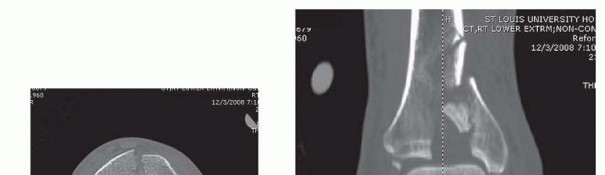

Radiographs of the knee and ankle are necessary to evaluate any articular fracture involvement or associated knee or ankle subluxation or dislocation. Identifying any occult fracture lines aids in the preoperative planning of potential pin placement. Many patients with high-energy tibial fractures have associated foot injuries, and views of the foot and ankle are necessary to identify this injury pattern. Traction radiographs of articular injuries of the tibia are useful to identify the nature and orientation of metaphyseal fragments as well as degree of articular impaction. This aids in determining whether a joint-spanning fixator is necessary. Distraction computed tomography (CT) scans should be obtained

after

the knee- or ankle-spanning fixator has been applied. These studies indicate the effectiveness of the ligamentotaxis reduction. This allows the surgeon to determine the preoperative plan for definitive fixation once the soft tissues have recovered 14 ( FIG 5). 535

### FIG 5 •

(continued)

D,E. CT scan obtained post distraction in the frame provides valuable information to help determine the preoperative plan for delayed definitive reconstruction once the soft tissues have recovered.